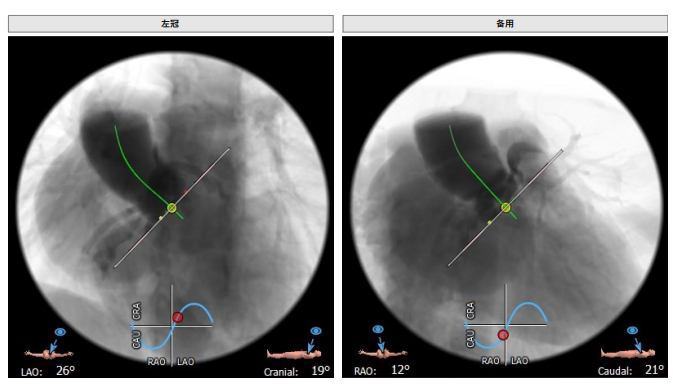

工作体位:LAO:12°CRA:5°,左冠切线位:LAO:26° CRA:19°

主动脉根部造影